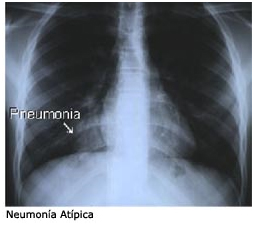

Medicina investiga prevalencia de neumonía en el HRE

La Neumonía es una infección respiratoria aguda que compromete el parénquima pulmonar. La severidad de la enfermedad varía desde cuadros leves hasta cuadros muy graves que comprometen la vida del individuo.

El aumento de la demanda de recursos de salud, pérdida de productividad de la población adulta y letalidad asociados a esta patología, han determinado que sea considerado un grave problema de salud pública tanto en nuestro medio como en el ámbito mundial.

La universitaria realizo un estudio descriptivo, observacional de corte transverso, con un muestreo no probabilístico de casos consecutivos, el número de pacientes internados en el mencionado periodo fue de 397, de los cuales 114 tuvieron neumonía (29%), el grupo de mayor afectación fue el de 41 a 60 años. En cuanto al sexo el masculino correspondió al 55 % y el restante al sexo femenino. El tiempo de internación en un 80 % fue menos de 10 días, un 13 % estuvo internado de 11 a 15 días y el restante 7 % más de 15 días.

Al analizar las complicaciones, el 72 % no presento ninguna complicación durante su tratamiento, pero un 28 % presento complicaciones como ser neumonía bilobular, o neumonía con derrame.